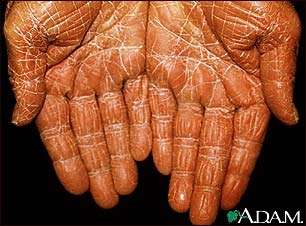

PRP is a chronic skin condition in which orange or salmon-colored scaly patches with thick skin develop on the hands and feet.

The scaly areas may cover much of the body. Small islands of normal skin (called islands of sparing) are seen within the areas of the scaly skin. The scaly areas may be itchy. There may be changes in the nails.